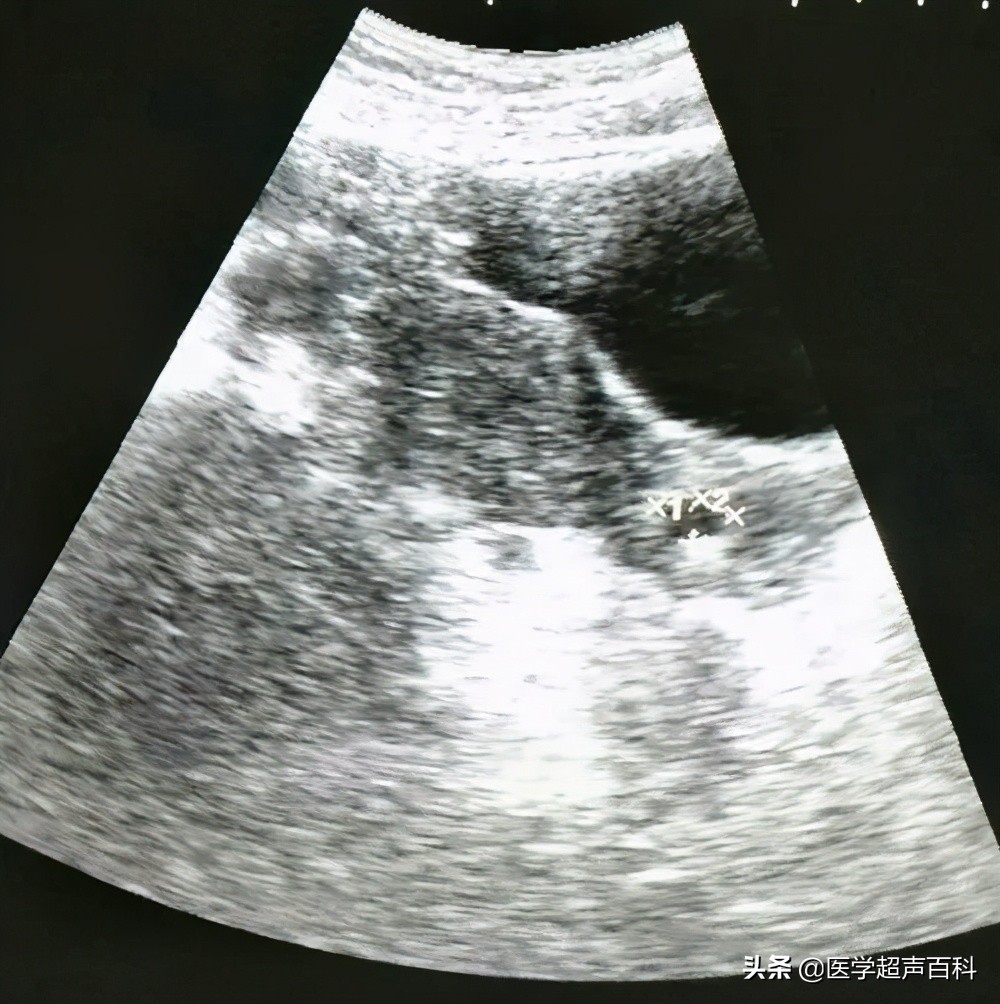

超声检查中,宫颈腺囊肿表现为宫颈前唇或后唇,外口或内口见单一或多个圆形或椭圆形、边界清晰、内部无回声的囊性结构。往往伴有宫颈肥大。